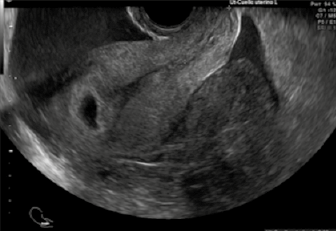

La subunidad β de la gonadotropina coriónica humana cualitativa se reportó positiva. El ultrasonido abdominal y endovaginal (Figuras 1 y 2) reportaron una gestación de 8.1 semanas, con saco gestacional en la cavidad endometrial, con feto único vivo de longitud cráneo-caudal de 1.66 cm. En el anexo izquierdo y el fondo de saco se observó una imagen heterogénea de bordes difusos de 10.6 x 6.6 x 9.5 cm, compatible con plastrón y 356 cc de líquido libre hipoecoico.

Figura 2 Corte sagital uterino en el que se observa la decidua y el embarazo intrauterino, a la derecha está el plastrón del embarazo ectópico en la salpinge izquierda y líquido libre de 356 cc.